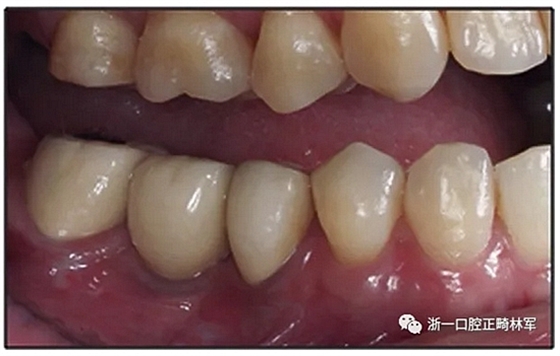

圖11.38個(gè)月時(shí)上頜與治療前的對(duì)比

經(jīng)過(guò)32個(gè)月的活動(dòng)治療后,上下牙弓排齊良好,下頜第一磨牙區(qū)的雙側(cè)牙間隙可用于種植(圖12,A和13,A)。